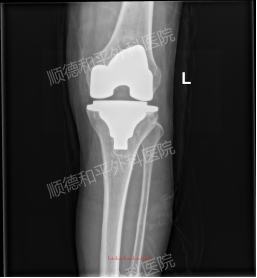

精准解决病灶,恢复关节功能:手术无需切除整个膝关节,仅对受损的股骨髁、胫骨平台表面进行处理,通过植入4号股骨髁假体、4号胫骨平台假体与6mm厚胫骨垫片,重建关节结构。术中通过骨水泥固定假体,确保假体与骨界面紧密贴合,术后C臂机透视显示假体位置满意,膝关节稳定性与活动度均恢复良好,从根本上解决关节疼痛与活动受限问题。

创伤可控,术后恢复快:患者术中出血仅100ml,远低于传统大手术的出血风险,且术后可早期下地行走。相比保守治疗长期依赖药物、效果反复的困境,手术能快速打破“疼痛-活动减少-关节退变加重”的恶性循环,让她更快回归正常生活。